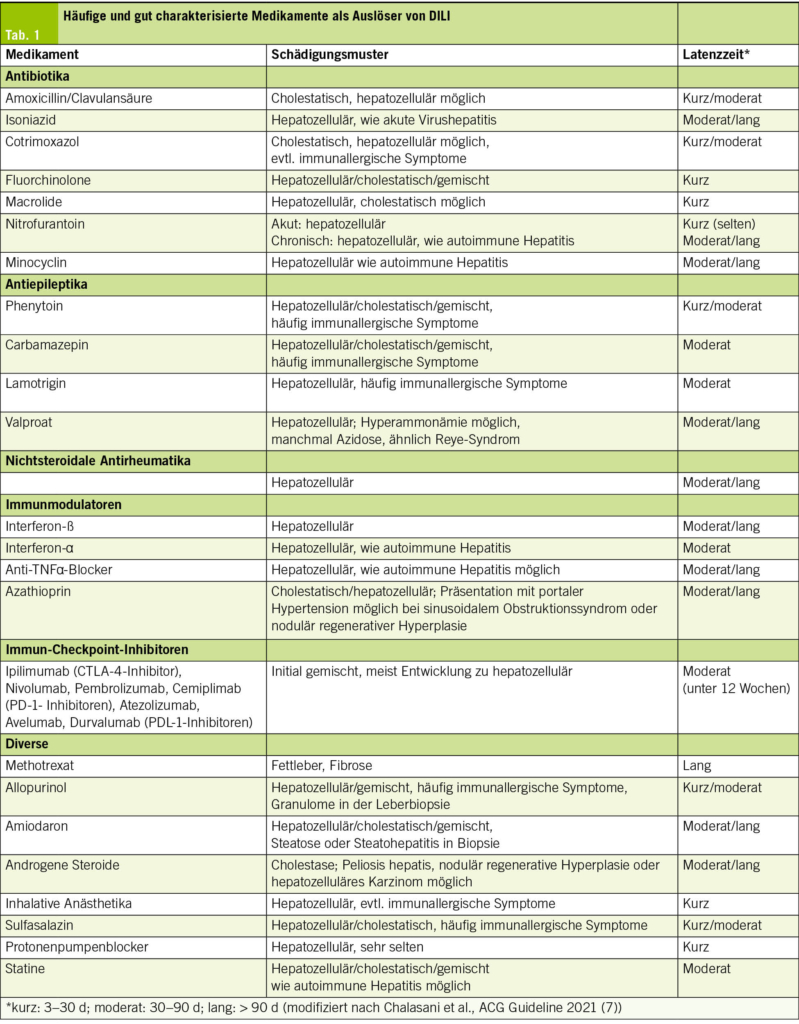

DILI ist eine Ausschlussdiagnose; eine sorgfältige Medikamenten- und Supplementenanamnese ist essenziell und muss auch frei verkäufliche Präparate und pflanzliche Produkte einschliessen. Dabei sollte gezielt nach neu begonnenen Therapien, Dosisänderungen und selbstmedizinierten Substanzen gefragt werden. Eine Übersicht häufiger und gut charakterisierter auslösender Medikamente findet sich in Tab. 1. Die häufigsten Substanzen in einem amerikanischen DILI-Register waren Amoxicillin/Clavulansäure, Isoniazid, Nitrofurantoin, Cotrimoxazol, Minocyclin, Cefazolin, Azithromycin, Ciprofloxacin, Levofloxacin, Diclofenac, Phenytoin, Methyldopa und Azathioprin (absteigende Reihenfolge; (3)). Antibiotika waren auch in einer europäischen Multicenterstudie die häufigsten DILI-Auslöser; als häufigste Einzelpräparate fanden sich Amoxicillin/Clavulansäure, Flucloxacillin, Atorvastatin, Nivolumab/Ipilimumab, Infliximab und Nitrofurantoin (16). Eine umfangreiche Übersicht potenziell hepatotoxischer Arzneimittel ist über die Plattform LiverTox verfügbar (www.ncbi.nlm.nih.gov/books/NBK547852/).

Schädigungsmuster und klinische Bedeutung des R-Werts